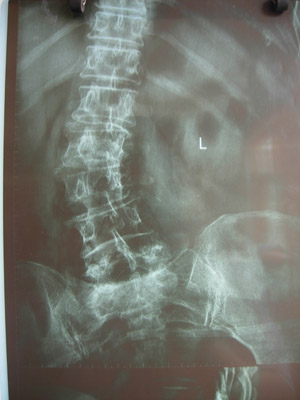

病例二

术前X线片